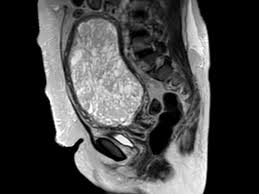

Mri Is Indicated In Patients With Malignant Forms Of Gestational Trophoblastic Neoplasia Gtn For An Assessment Of Tumor Vasc Rings For Men Mri Representation

The latter four entities are referred to as gestational trophoblastic neoplasia GTN. A common characteristic of all gestational trophoblastic disease is an abnormal proliferation of trophoblast but different components predominate in different tumors. Ultrasound remains the radiological investigation of choice for initial. Gestational trophoblastic neoplasia GTN encompasses a broad spectrum of placental lesions from the pre-malignant hydatidiform mole complete and partial through to the malignant invasive mole choriocarcinoma and rare placental site trophoblastic tumour PSTT. The latter four entities are referred to as gestational trophoblastic neoplasia GTN. There are several histologically distinct types of GTD that range from premalignant complete and partial hydatidiform moles HMs to malignant diseases also known as gestational trophoblastic. Ultrasound in the Diagnosis and Management of GTN Gestational trophoblastic neoplasia GTN includes invasive mole choriocarcinoma PSTT and ETT. Because it is an unusual and serious disease that affects women of reproductive age as well as because its appropriate treatment results in high cure rates it is crucial that radiologists be familiar with gestational trophoblastic disease in order to facilitate its early diagnosis and to ensure appropriate follow-up imaging. Gestational trophoblastic disease GTD is a spectrum of both benign and malignant gestational tumors including hydatidiform mole complete and partial invasive mole Choriocarcinoma placental site trophoblastic tumor and epithelioid trophoblastic tumor.

Gestational trophoblastic disease GTD encompasses a heterogeneous group of lesions including hydatidiform mole invasive mole choriocarcinoma and placental site trophoblastic tumor Mazur and Kurman 1994. The term gestational trophoblastic disease GTD encompasses a spectrum of tumors with a wide range of biologic behavior and potential for distant metastases. Gestational trophoblastic disease GTD is a term used for a group of pregnancy-related tumours. GTD refers to both the benign and malignant entities in the spectrum and includes hydatidiform mole complete and partial invasive mole choriocarcinoma placental site trophoblastic tumor PSTT and epithelioid trophoblastic tumor ETT. There are several histologically distinct types of GTD that range from premalignant complete and partial hydatidiform moles HMs to malignant diseases also known as gestational trophoblastic. Ultrasound in the Diagnosis and Management of GTN Gestational trophoblastic neoplasia GTN includes invasive mole choriocarcinoma PSTT and ETT. GTD refers to both the benign and malignant entities in the spectrum and includes hydatidiform mole complete and partial invasive mole choriocarcinoma placental.